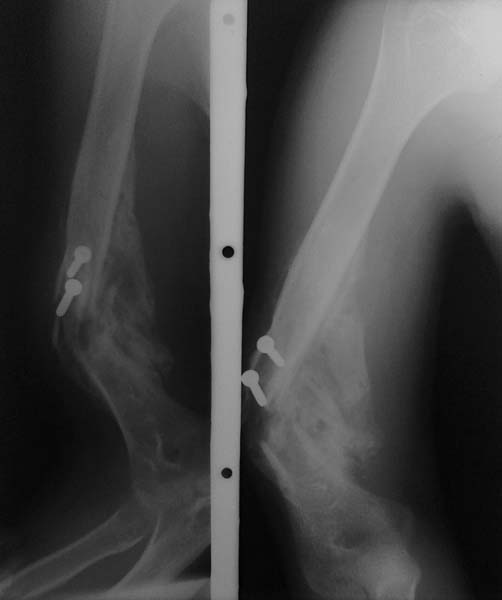

Уважаемые коллеги! Пациент П 26 лет, на учете у невропатолога по поводу ДЦП. Больной психологически неадеватный. Около 5 мес назад оперирован в одной из ЦРБ по поводу закрытого винтобразного перелома плечевой кости. Произведено открытая репозиция, фиксация отломков компрессирующими винтами. Через 1,5 мес при судорожном приступе упал и получил рефрактуру. В данный момент имеется выраженная угловая деформация плеча, в проекции деформации-рана 1,5х1,0 см, покрыта коркой, из ран выступает острый конец проксимального отломка (на рентгенограмме видно), отделяемое из ран нет. Потологический подвижность нет. Клинические признаки повреждения лучевого нерва. Помогите определить тактику лечения. Заранее благодарен...

В какой-то степени похожий случай демонстрировался на форуме 27 апреля 2010г. Все сейчас зависит от задач, которые Вы и Ваш пациент ставите перед собой. Возможно, достаточно сделать краевую резекцию выступающего в рану участка плечевой кости. Если рядом винты (по снимку не очень понятно, могут ли они поддерживать воспалительный процесс) - удалить и их. И желательно понять, что явилось причиной повреждения лучевого нерва. Если он не был поврежден во время операции, тогда консервативное лечение (шина, удерживающая кисть в физиологическом положении, ЛФК и т.д.) должно дать медленный и неполный, но положительный результат. Если же Вы ставите перед собой задачу устранить деформацию, стоит сто раз подумать, нужно ли так рисковать.

Удалите винты, проведите некрэктомию (возможно с ревизией нерва), добейтесь нормального состояния покровов. После этого остеотомия, восстановление проходимости КМ канала и интрамед. остеосинт.